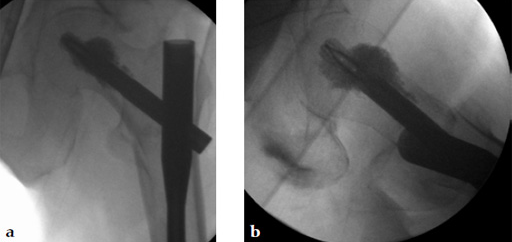

After finishing the usual procedure of inserting the nail and the perforated blade, a leakage into the joint has to be excluded by injection of contrast medium through the perforated blade first. Then the prefilled side opening cannula is inserted into the blade and the position checked by image intensifier. A medial perforation must be avoided. Furthermore, the special 1 ml syringe is adapted to the cannula (Fig 6) and the cement can be injected (Fig 7). By turning the cannula the positioning of the cement around the helical blade can be navigated. Around 36 ml of cement should be injected. The whole injection procedure must be done under image intensifier control.

An 82-year-old woman with an unstable pertrochanteric fracture of the right proximal femur. Her Barthel Index was 80 and her preoperative Parker mobility score was 5, which means that she was walking at home unassisted. The patient's preoperative Parker mobility score of 5 was reached again at the 3-month follow-up.